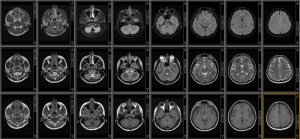

Brain Connectivity in Cognitive Aging: A primer on concept, measurement, and application

Patrick J. Pruitt, PhD

mri mri

Join us for the Neuroimaging Summer Seminar Series, showcasing the cutting-edge research of the neuroimaging faculty at the Michigan Alzheimer's Disease Research Center. This series aims to inspire both students and faculty to incorporate imaging techniques into their research, while highlighting the pivotal contributions to neurodegeneration disease studies. Don't miss this opportunity to explore the forefront of neuroimaging research.